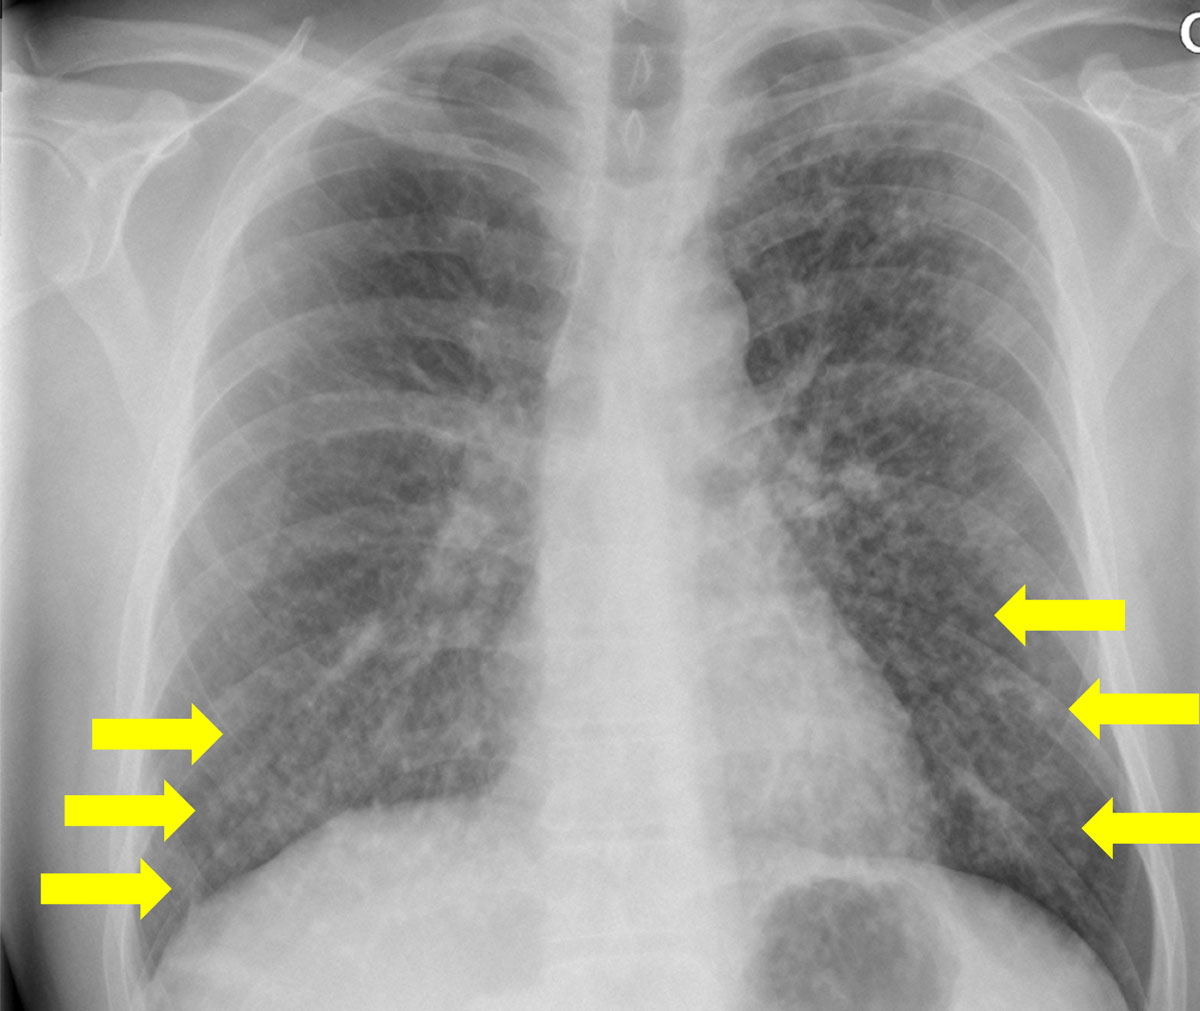

The patterns for each chest radiograph were recorded (table 3). Overall, there were no differences in patterns between the two cohorts according to the Bonferroni corrected results. However, the results from the logistic regression model showed that there was a significantly higher prevalence of reticulation in RTRs as compared with HIV patients (95.7 ± 4.2% vs 86.0 ± 4.5%; table 3). Consolidations and solid nodules were found in 47.8 ± 10.2% and 4.3 ± 4.2% of RTRs, respectively. Consolidation and multiple nodules were more prevalent in the HIV-positive patient cohort (fig. 4). For the pattern distribution within the lung lobes, we found that the basal lungs, namely, middle lobe, lingula and lower lobes, were significantly more affected in HIV-positive patients (75.0 ± 5.6% vs 58.7 ± 10.1% in RTRs p = 0.021; fig. 5). In particular, the middle lobe was mainly involved in the HIV-positive cohort (64.0 ± 6.2% vs 17.4 ± 7.7% in RTRs, p = 0.006; table 3).

Figure 4 Bilateral nodular consolidation in a human immunodeficiency virus -positive patient.

Figure 5 Faint homogeneous central ground glass opacity with sparing of the caudal lungs/sinus phrenicocostalis (arrows) in a renal transplant patient.